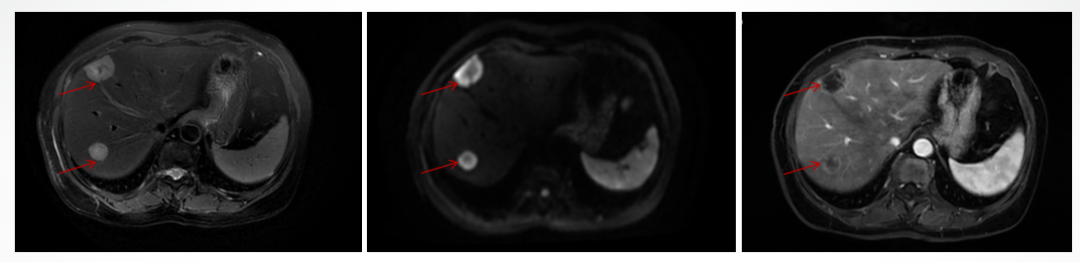

2022-01-23肝脏增强MR示:肝IV段及右叶见多发结节状、团片状长T1、长T2信号灶,DWI及ADC示弥散受限,增强扫描见边缘强化或结节状强化,较大者位于IV段,大小约29mm×21mm。附见:脊柱及两侧肋骨多发异常强化灶,考虑转移。

肝脏肿块:低分化腺癌,考虑乳腺癌转移。

免疫组化结果:AFP-,HepPar-1-,GATA-3散在+,ER个别+,PR个别+,Ki-67 20%,c-erbB-2(BC)3+,CK7+,CK20-,CDX2-,Arginase-1-,GPC3-。